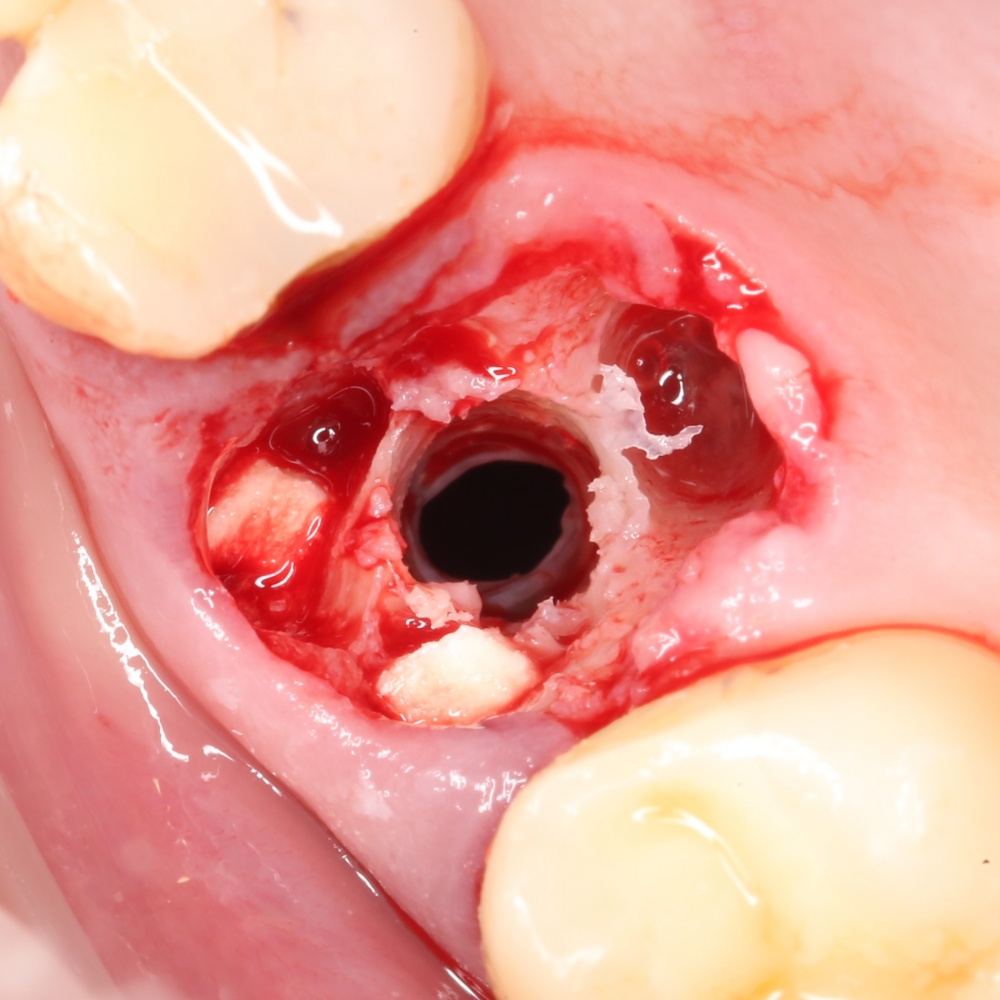

Изоляция области аутографта и имплантатов барьерной мембраной.

Перекрывать костный блок барьерной мембраной или оставить так? По этому вопросу есть много мнений. Между тем, в публикации по методике есть ясное показание, когда это требуется.

Конкретно в этом клиническом случае между костным аутотрансплантатом, ложем и имплантатами есть пустое пространство. Если его не изолировать от мягких тканей, они прорастут и осложнят интеграцию аутографта. Поэтому я решил перекрыть костный блок барьерной мембраной, пусть это делает хирургическую операцию немного дороже.

На этом этапе есть несколько нюансов, о которых я хочу рассказать отдельно.

— я использовал барьерную мембрану Geistlich Bio-Gide, которая имеет две разные поверхности: с одной стороны она рыхлая «адгезивная», с другой — гладкая и прочная. Как укладывать — на результат не влияет, но в плане удобства рыхлую поверхность мы «приклеиваем» к тому, на чем требуется барьерную мембрану удержать. В данном случае хотелось бы удержать её на костной поверхности — следовательно, мы укладываем её рыхлой поверхностью к кости.

— много лет мы используем антибиотики для интраоперационной профилактики инфекционно-воспалительных осложнений. Уже в то время мы пришли к выводу, что удобнее всего — порошки антибактериальных препаратов для приготовления раствором: дешевые, стерильные, в удобной упаковке. Прямо в виде порошка их можно добавлять в графт, растворы для ирригации, либо использовать так, как показано на фото. Еще мы используем порошок антибиотика для изготовления пасты, которой обрабатываем имплантаты в процессе ревизии или при лечении периимплантита. Это удобнее и эффективнее, чем интраоперационное использование жидких форм антибактериальных препаратов.

— ты знаешь, что барьерная мембрана может выполнять две функции, каркасную и изолирующую. Первая функция требует обязательной фиксации и натяжения, вторая — нет. В нашем случае «каркасом» регенерата является костный блок, а барьерная мембрана нужна только для изоляции. Поэтому она не требует натяжения и фиксации пинами.

После я внимательно проверил, что костный блок и имплантаты полностью перекрыты. Теперь рану можно ушивать.